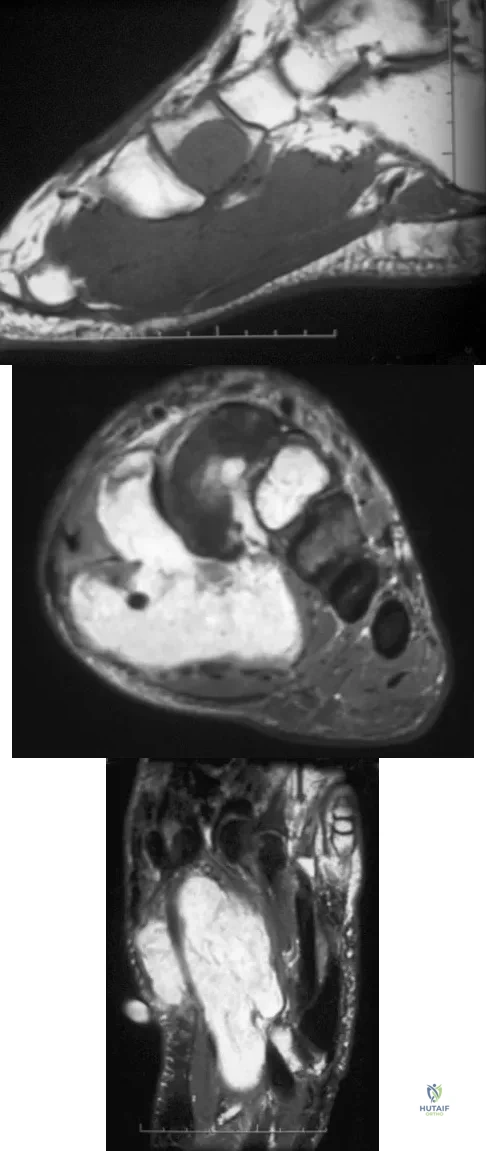

A 39-year-old man has had a foot mass for the past several months. MRI scans are shown in Figures 78a through 78c. A core biopsy specimen reveals synovial sarcoma, and a staging chest CT scan is normal. Which of the following treatments offers the best local tumor control and expedites the patient's return to normal function?

Explanation